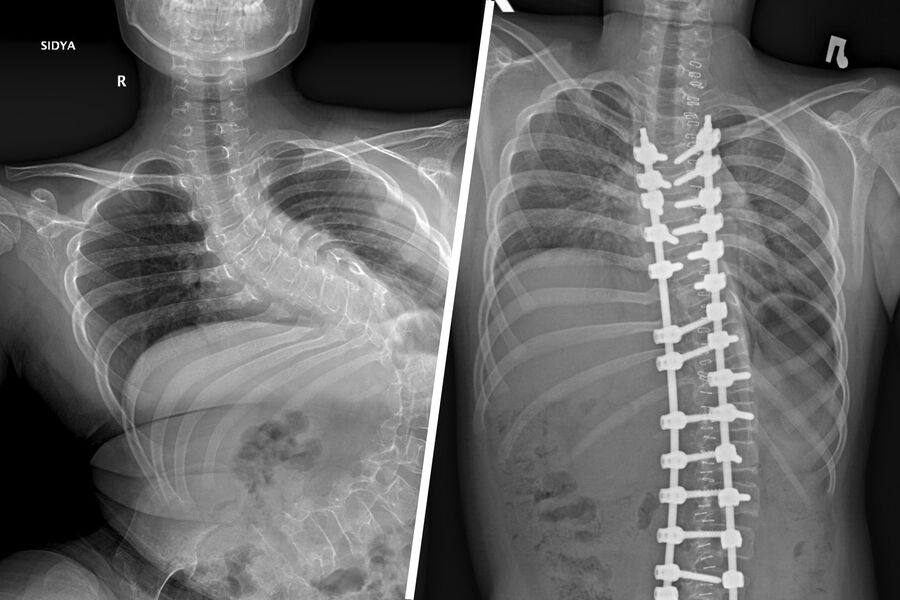

«Первым этапом хирургического лечения стала коррекция деформации позвоночника, поскольку она достигла уже критических значений — более 140 градусов искривления. Без своевременно выполненной операции сколиоз прогрессировал бы дальше, и мальчик не смог бы даже сидеть», — рассказал врач больницы Александр Васюра.

Вмешательство длилось четыре часа: за это время ребенку скрепили позвоночник металлической конструкцией, скорректировав деформацию до 32 градусов.